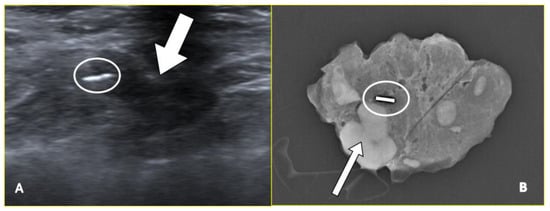

2.1. Marker Clips and Intraoperative Ultrasonography

- Siso, C.; de Torres, J.; Esgueva-Colmenarejo, A.; Espinosa-Bravo, M.; Rus, N.; Cordoba, O.; Rodriguez, R.; Peg, V.; Rubio, I.T. Intraoperative Ultrasound-Guided Excision of Axillary Clip in Patients with Node-Positive Breast Cancer Treated with Neoadjuvant Therapy (ILINA Trial): A New Tool to Guide the Excision of the Clipped Node After Neoadjuvant Treatment. Ann. Surg. Oncol. 2018, 25, 784–791. [Google Scholar] [CrossRef]

- Boughey, J.C.; Ballman, K.V.; Le-Petross, H.T.; McCall, L.M.; Mittendorf, E.A.; Ahrendt, G.M.; Wilke, L.G.; Taback, B.; Feliberti, E.C.; Hunt, K.K. Identification and Resection of Clipped Node Decreases the False-Negative Rate of Sentinel Lymph Node Surgery in Patients Presenting With Node-Positive Breast Cancer (T0-T4, N1-N2) Who Receive Neoadjuvant Chemotherapy: Results From ACOSOG Z1071 (Alliance). Ann. Surg. 2016, 263, 802–807. [Google Scholar] [CrossRef] [PubMed]

- Caudle, A.S.; Yang, W.T.; Krishnamurthy, S.; Mittendorf, E.A.; Black, D.M.; Gilcrease, M.Z.; Bedrosian, I.; Hobbs, B.P.; DeSnyder, S.M.; Hwang, R.F.; et al. Improved Axillary Evaluation Following Neoadjuvant Therapy for Patients With Node-Positive Breast Cancer Using Selective Evaluation of Clipped Nodes: Implementation of Targeted Axillary Dissection. J. Clin. Oncol. Off. J. Am. Soc. Clin. Oncol. 2016, 34, 1072–1078. [Google Scholar] [CrossRef] [PubMed]